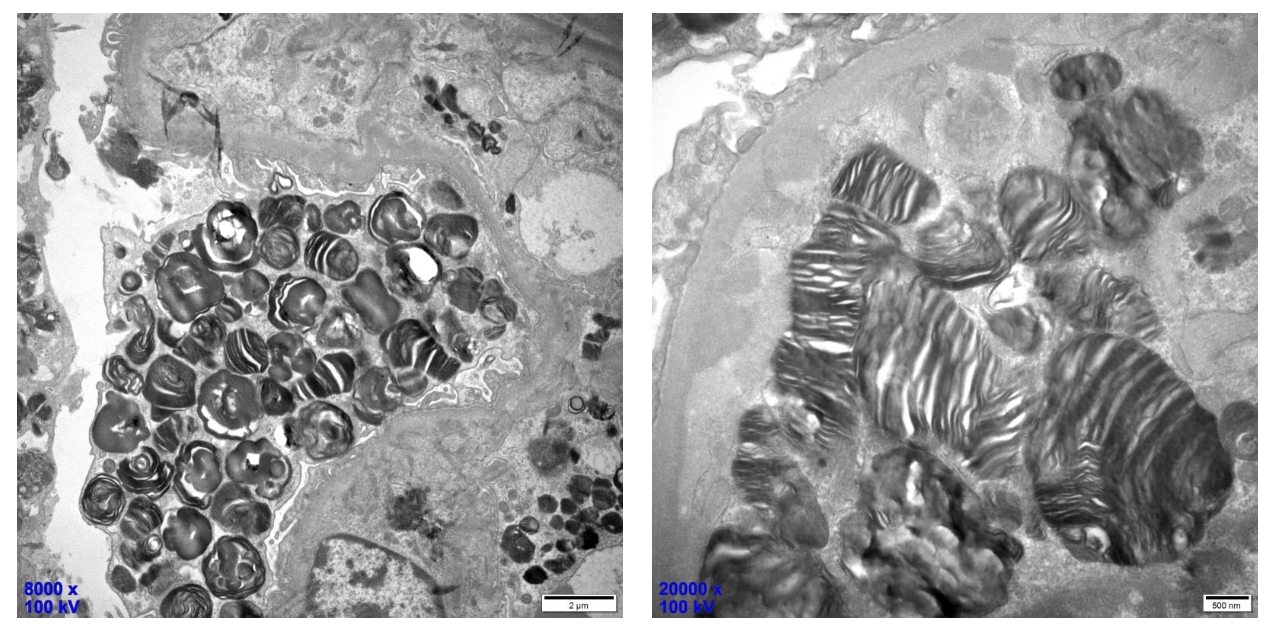

电镜下具有特征性改变,即肾脏各种细胞的细胞质内均可充满嗜锇“斑马小体”。(以上两张图组)

该“斑马小体”呈较高电子密度,圆形或卵圆形,直径1~5um,小体内部呈层状,层间距较一致,形似斑马皮,亦似洋葱皮、层状结构或髓鞘样结构,故称“斑马小体”“洋葱皮小体”“片层样小体”或“髓样小体”,当该小体被包含在溶酶体中,周围由一层膜包绕,为Fabry病特征性表现。(以上两张图组)

各种细胞的细胞质内均可见,包括肾小球脏层上皮细胞、壁层细胞、肾小管上皮细胞、肾间质细胞、血管壁内皮细胞和平滑肌细胞(以上六张图组)

电子显微镜(EM)被认为是唯一可用于可靠确认或排除Fabry肾病的工具:

»在不同细胞类型的溶酶体内观察到GL-3沉积物称为“髓鞘图”、“洋葱皮”或“斑马体” 。

»在高放大倍率下,GL-3沉积物由电子致密的多层同心层组成,3.5至5nm具有诊断意义,可见足细胞内大量分层环状的髓磷脂样小体(又称髓样小体)。